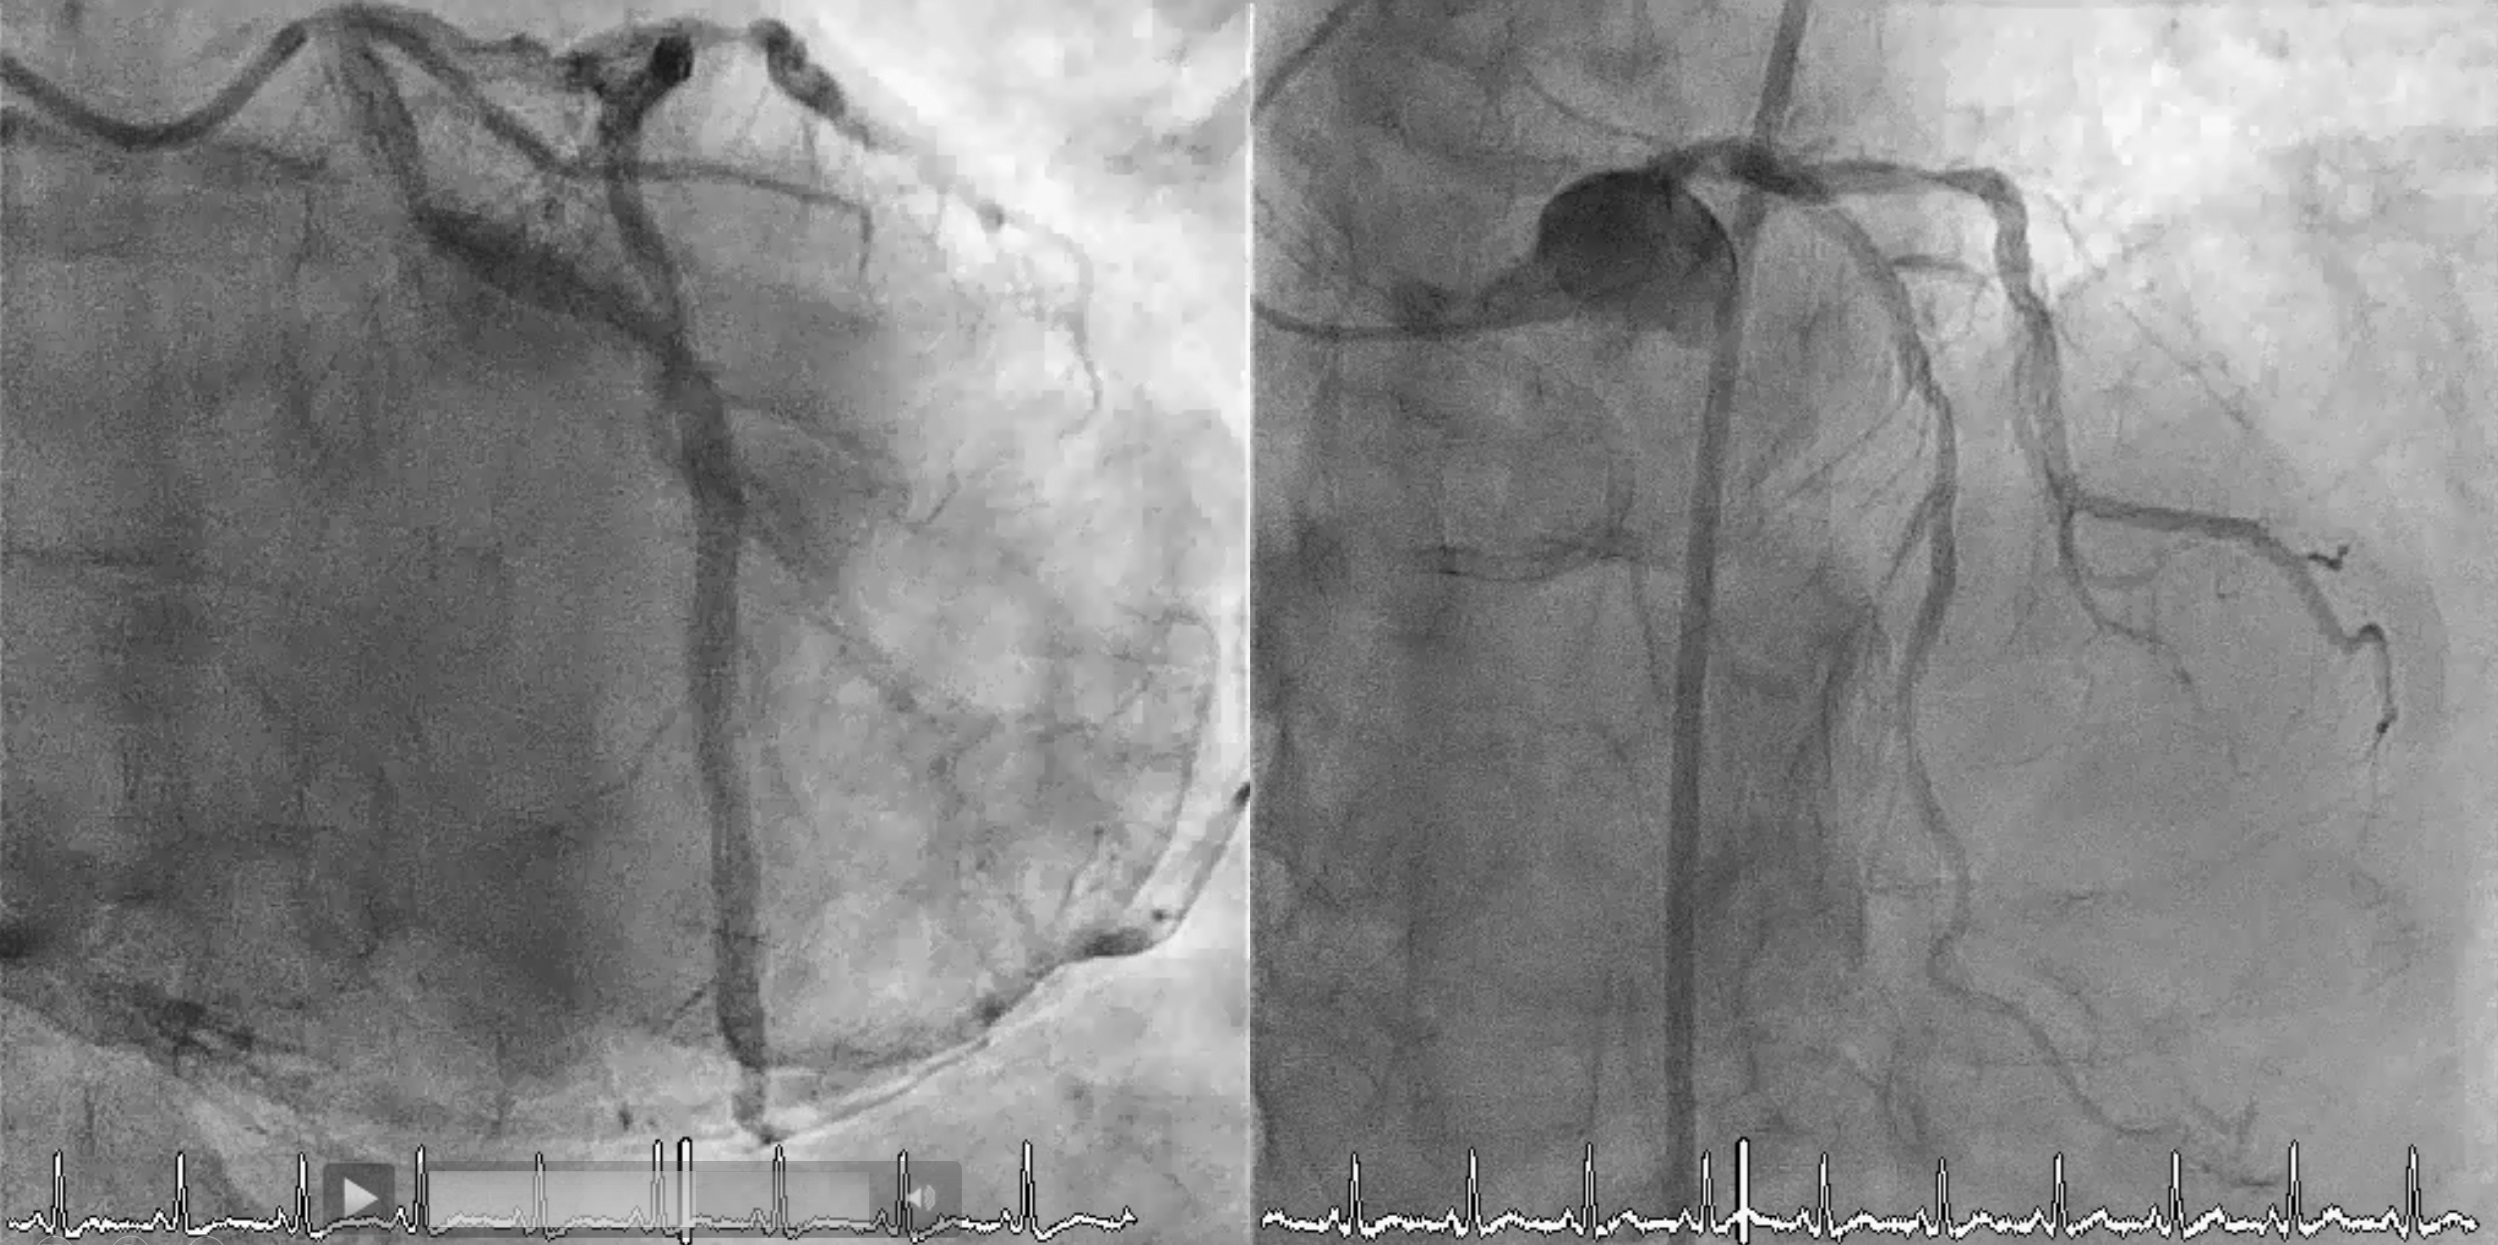

Diagnosticcoronary angiography revealed: Chronic total occlusion (CTO) in the rightcoronary artery (RCA) with heavy calcification; Diffuse lesion in the leftanterior descending (LAD) artery; Proximal lesion in the left circumflex (LCx)artery; LAD providing collateral flow to the RCA.

First Procedure: An antegrade approach was initially attempted with wire escalation strategies (using XTA, Fielder FC, Gaia I, II, III, Conquest pro in Cosair), but the wire entered a false lumen. Shift to parallel wire technique with Sasuke. The Gaia III wire eventually reached the distal true lumen. Balloon dilation was attempted, but the CTO segment remained undilatable. IVUS confirmed severe calcification, so a 1.25 mm rotational atherectomy (ROTA) burr was used, which led to mild improvement but still left an undilatable lesion. The procedure was paused because the patient could not tolerate lying flat for an extended time.Second Procedure was performed 3 months later. RCA still showed stenosis despite receiving collateral flow from LAD. Balloon dilation attempts were unsuccessful, necessitating a shift to a 1.75 mm ROTA burr for further plaque modification.After successful lesion modification, further preparation for stenting was performed, followed by the deployment of a 3.0 x 48 mm and a 3.5 x 48 mm drug-eluting stent (DES) in the RCA. Final IVUS confirmed adequate stent placement with good distal runoff. Additional stenting was performed in the LCx and LAD.